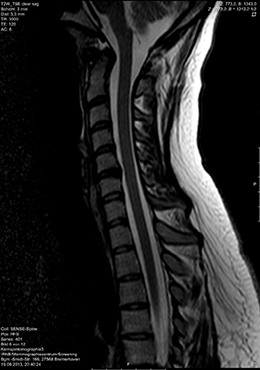

In der MRT, die auch als Kernspintomographie bezeichnet wird, kommen keine radioaktiven Strahlen zum Einsatz. Die Bildgebung erfolgt durch Signale, die für den Menschen unschädlich sind. Mit Hilfe eines außerordentlich starken Magnetfeldes werden die Wasserstoffkerne in den Molekülen der verschiedenen Gewebe des Körpers wie Kompassnadeln ausgerichtet. Durch Änderung des Magnetfeldes und wiederholter Sendung von Frequenzimpulsen schwingen sie in ihre ursprüngliche Lage wieder zurück, wobei sie ihrerseits Signale aussenden, die in einem Hochleistungscomputer in Schnittbilder umgewandelt werden.

Die MRT ist hinsichtlich der Darstellbarkeit von verschiedenen Organen, Gefäßen, Bändern und Gelenken vielen anderen heute in der Radiologie zur Verfügung stehenden bildgebenden Verfahren überlegen. Insbesondere Entzündungsherde und vitale Tumoren können mit der MRT häufig besser erkannt werden als mit anderen Verfahren.